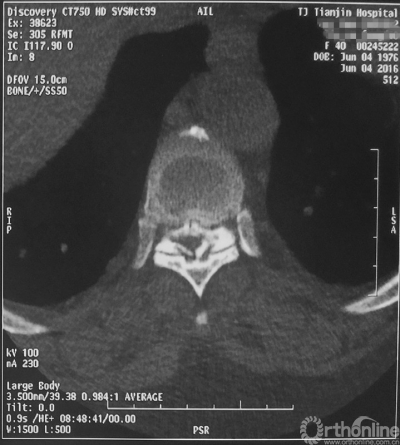

术前MRI

家人曾带她辗转当地治疗,因病情复杂没有得到有效的治疗,于是慕名找到天津医院脊柱外科二病区主任苗军博士诊治,当苗军主任看到躺在担架上的刘女士痛苦的表情和渴望健康的眼神,他决定收她入院为其进行手术治疗。入院检查发现,刘女士患有多节段胸椎管狭窄症,以胸8-9节段严重,椎管狭窄达80%,脊髓已严重变性。